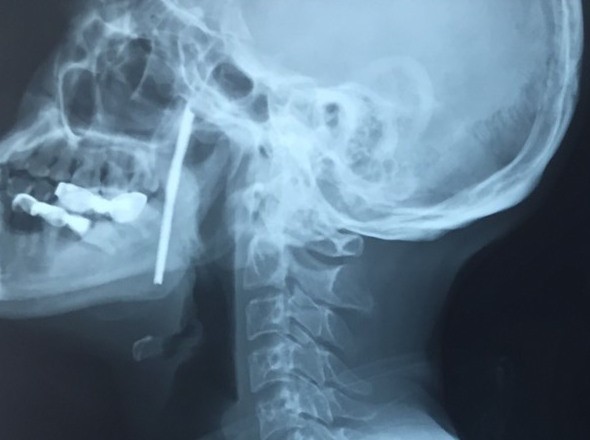

Ảnh chụp X-quang bệnh nhân bị thanh sắt cắm xuyên cổ. Ảnh: BVCC

Bệnh viện Hữu nghị Việt Đức cho biết, bệnh nhân L.V.T., 40 tuổi, sống ở Sơn La bị một thanh sắt dài 10 cm cắm vào chính giữa vùng cổ trong lúc lao động.

Ngay sau khi tiếp nhận bệnh nhân, TS. Vũ Ngọc Tú - Trung tâm Phẫu thuật Tim mạch và Lồng ngực, Bệnh viện Hữu nghị Việt Đức – chẩn đoán bệnh nhân bị vết thương phức tạp vùng cổ do thanh sắt kim loại dài, xiên từ hầu họng vào trong miệng - là vùng có rất nhiều cơ quan hệ trọng của cơ thể như đường thở (khí quản), đường ăn (thực quản), các mạch máu nuôi não (động mạch cảnh).

May mắn, thanh sắt chưa trực tiếp gây tổn thương các vùng quan trọng của cơ thể nhưng lại nằm sát cạnh các vùng đó. Vì thế, các bác sĩ phải lấy bằng được dị vật nhưng vẫn đảm bảo an toàn tuyệt tính mạng người bệnh, đồng thời, giữ được các chức năng của cơ thể.